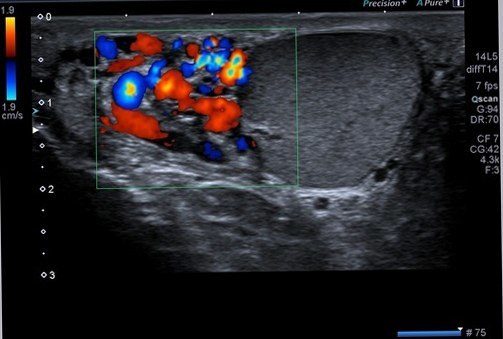

Erişkin erkeklerde testis kist ve kitlelerini, kese içerisindeki sıvı miktarını, damarsal genişlemeleri (varikosel), kese içerisinde testislerin komşuluğunda yerleşimli epididim enfeksiyonlarını değerlendirmede bu yöntem ilk tercihtir.

Varikosel için renkli doppler ultrasonu incelemesi de gerekecektir.